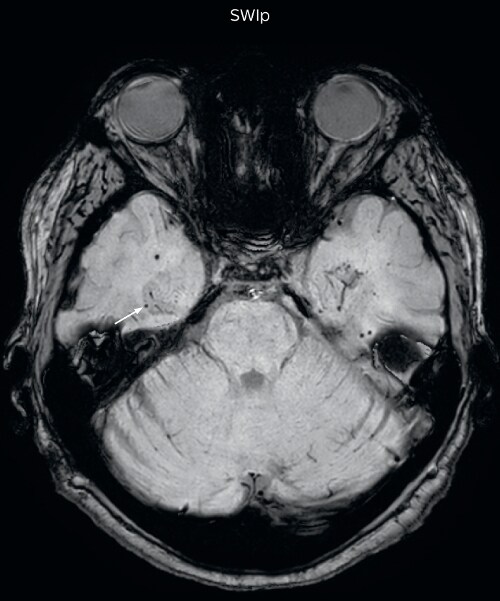

Gradient echo imaging and SWIp are compared in a patient with radiation-induced foci of hemosiderin deposition. A greater number of small foci is seen on the SWIp image. Ingenia 3.0T

“With SWIp we are basically looking for blood byproducts. It is a sensitive method for visualizing small lesions containing deoxygenated blood. In our comparison, SWIp images are vastly better than gradient echo imaging, there’s no question of that anymore.” “We find the SWIp images very useful in three areas in particular. In patients with a history of hypertension, it offers clear visualization of hemosiderin deposition from hypertensive hemorrhages. We certainly see a greater number of foci of hemosiderin deposition on the SWIp images than on the T2* gradient echo images. In addition, it also helps us visualize amyloid depositions in patients with amyloid angiopathy.” Dr. Nickerson mentions trauma patients are the third large area where SWIp is useful. “We benefit from SWIp in trauma patients, certainly in cases with diffuse axonal injury and shearing injuries. Our study shows that SWIp usually provides us better visualization,” he says. “Apart from these three, SWIp also helps us to beautifully depict the normal venous anatomy in patients with venous outflow issues or vascular congestion. In some cases, we have seen downstream effects of arterial problems. And in patients with vascular malformations we have seen deposition of blood products associated with those.”

“We switched over entirely. SWIp is now included in all our routine brain exams. We developed two different SWIp sequences: a high spatial resolution (0.5 x 0.5 mm) version that takes 5.5 minutes and our fast SWIp that takes just three minutes. Only in patients that are moving tremendously we occasionally still acquire a gradient echo sequence.” “For us, SWIp use has resulted in more diagnostic confidence when small lesions, such as small shear injuries, vascular malformations, or minute amounts of calcification, need to be detected,” says Dr. Nickerson. “Our physicians greatly value the SWIp images. When we get patients transferred from other facilities with SWIp missing from their exam, we have several neurologists and neurosurgeons who order a new MRI exam because they want to see the SWIp images.”